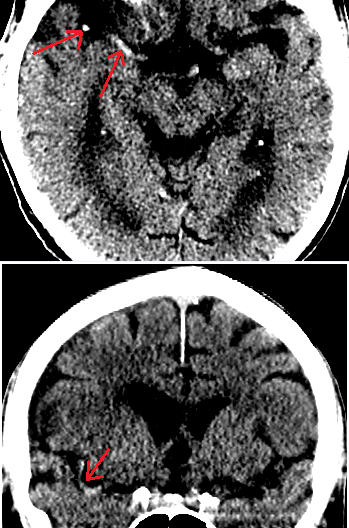

• “Dense MCA sign” is caused by opacification of the MCA by a thrombus. When noted this is likely to be in the horizontal body of the MCA coming off of the Circle of Willis, but more subtly can also be sometimes seen in a branch of the MCA. In the figure below the right MCA is dense and both an MCA “dot sign” as the MCA enters the Sylvian fissure and a linear section of MCA coming off the Circle of Willis and running along the skull base are visible in the axial cut. In the coronal section a long curved portion of the MCA is clearly visible.

Dense MCA sign in R hemisphere